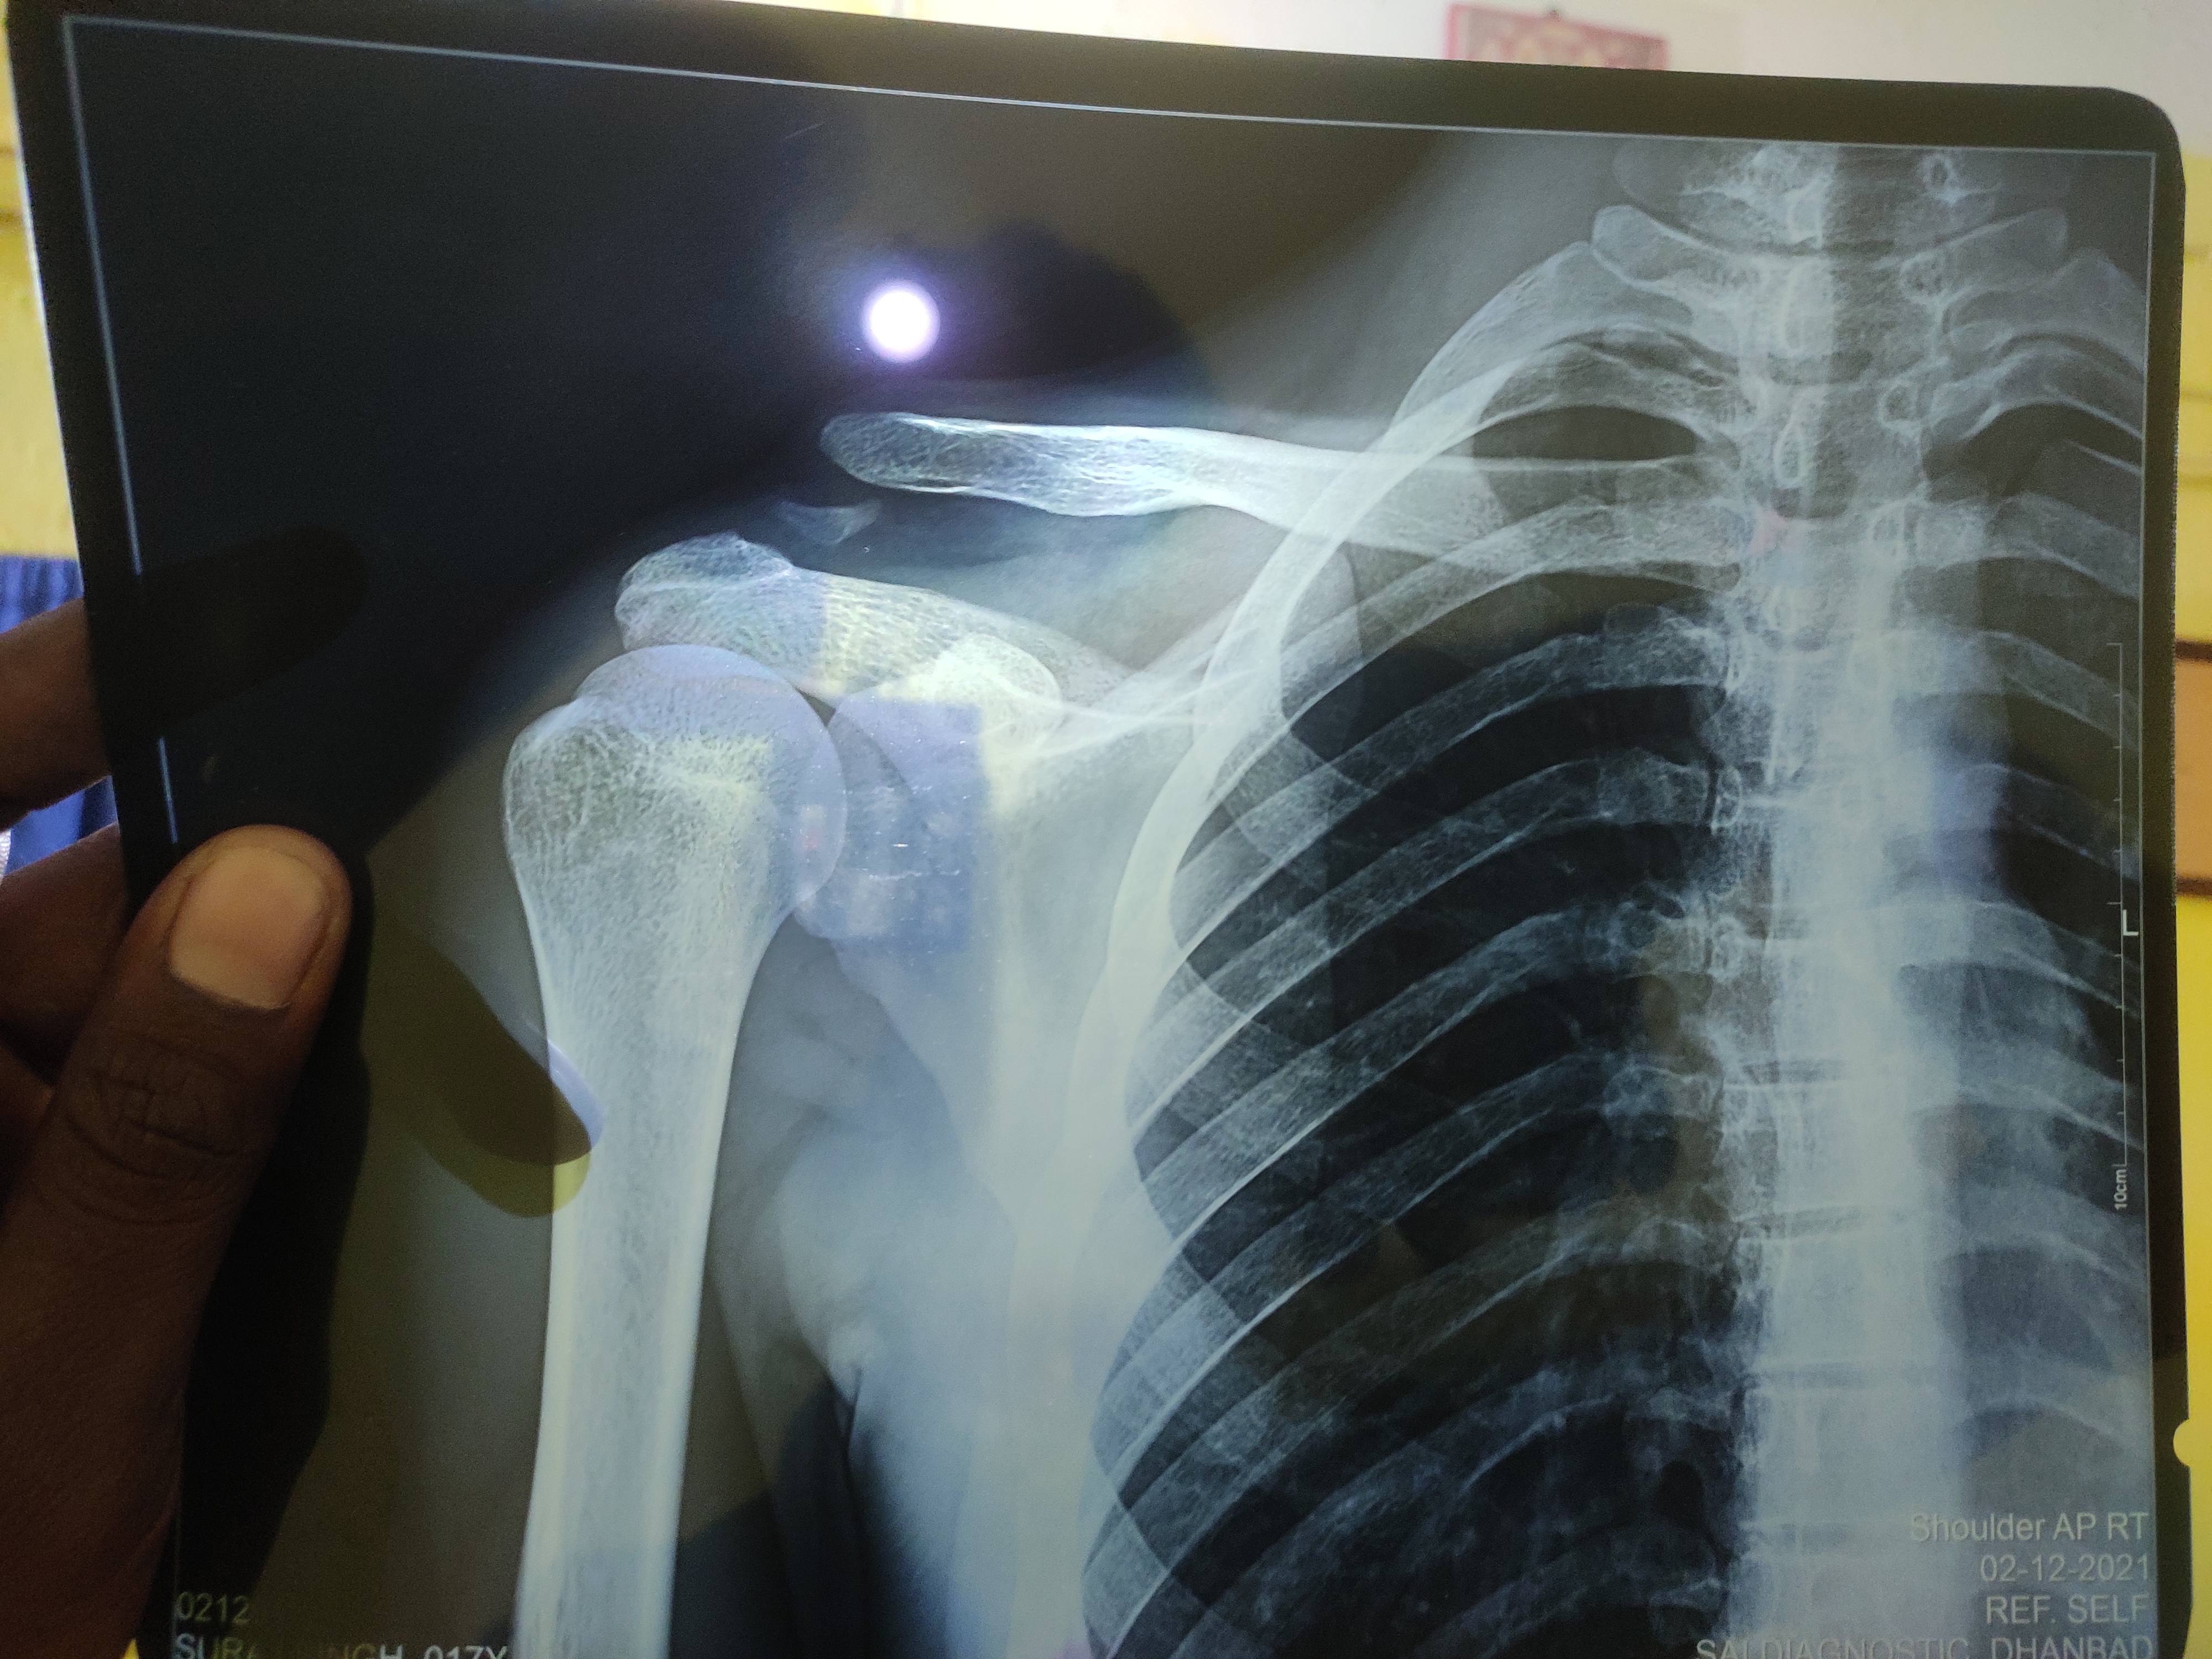

Clavicle fracture kya repair hoga naturally

Clavicle bone fracture

Sir ac joint dislocation hai kya krna hai